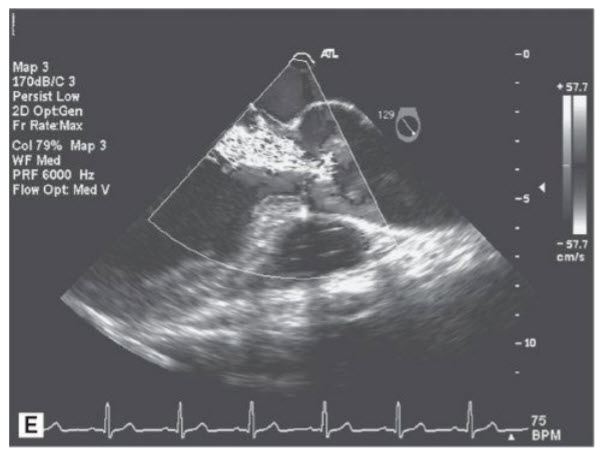

A 36-year-old man with a history of hypertension on medications for 5 years presents to your office with complaints of dyspnea on exertion and is found by his internist to have a heart murmur. Below are some representative views from his TTE (Figs. below A–E).

A. Suprasternal notch view in 2D (TTE). B. Suprasternal notch with color Doppler. C. Continuous-wave Doppler in the descending aorta from the suprasternal notch. D. Parasternal long-axis view in systole. E. Parasternal long-axis view with color Doppler.

Coarctation of the aorta with bicuspid AV with AI. The patient is a young man with hypertension beginning in his late 20s or early 30s. Secondary hypertension must be considered and ruled out in this patient. When he was initially diagnosed he should have had his blood pressure checked in both arms and legs in consideration of a coarctation of the aorta. Note: Someone may also notice rib notching on a chest X-ray. Other etiologies that should have been excluded include renal artery stenosis (more commonly seen in women if caused by fibromuscular dysplasia), pheochromocytoma, Cushing syndrome, or primary aldosteronism. This patient’s heart murmur was a diastolic murmur from AI caused by prolapse of a bicuspid AV. At least 50% of patients with a coarctation have a bicuspid AV. Fewer patients with bicuspid AV have a coarctation. Note that bicuspid AVs dome (doming aortic leaflets are seen in Fig. D in question) and could be mistaken on initial glance in long axis with a rheumatic AV. However, in addition to doming there is prolapse of the conjoined cusp (which would not be seen in a rheumatic valve) and the anatomic situation could be clarified with a good short-axis view.